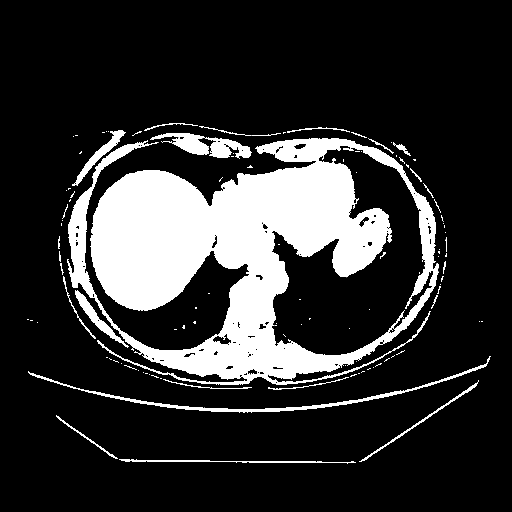

Original VENOUS CT scan

Full window (WL 1023.5, WW 4095 β†’ Low βˆ’1024, High +3071)

Actual HU range: [-1024.0, 3071.0]